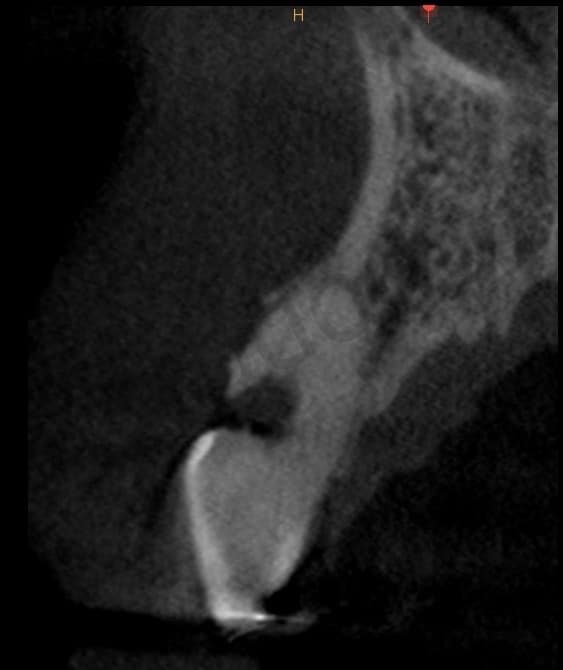

The cbct showed a lesion of about 4mm in diameter, which vestibularly affected the root #13, just below the junction.

CBCT